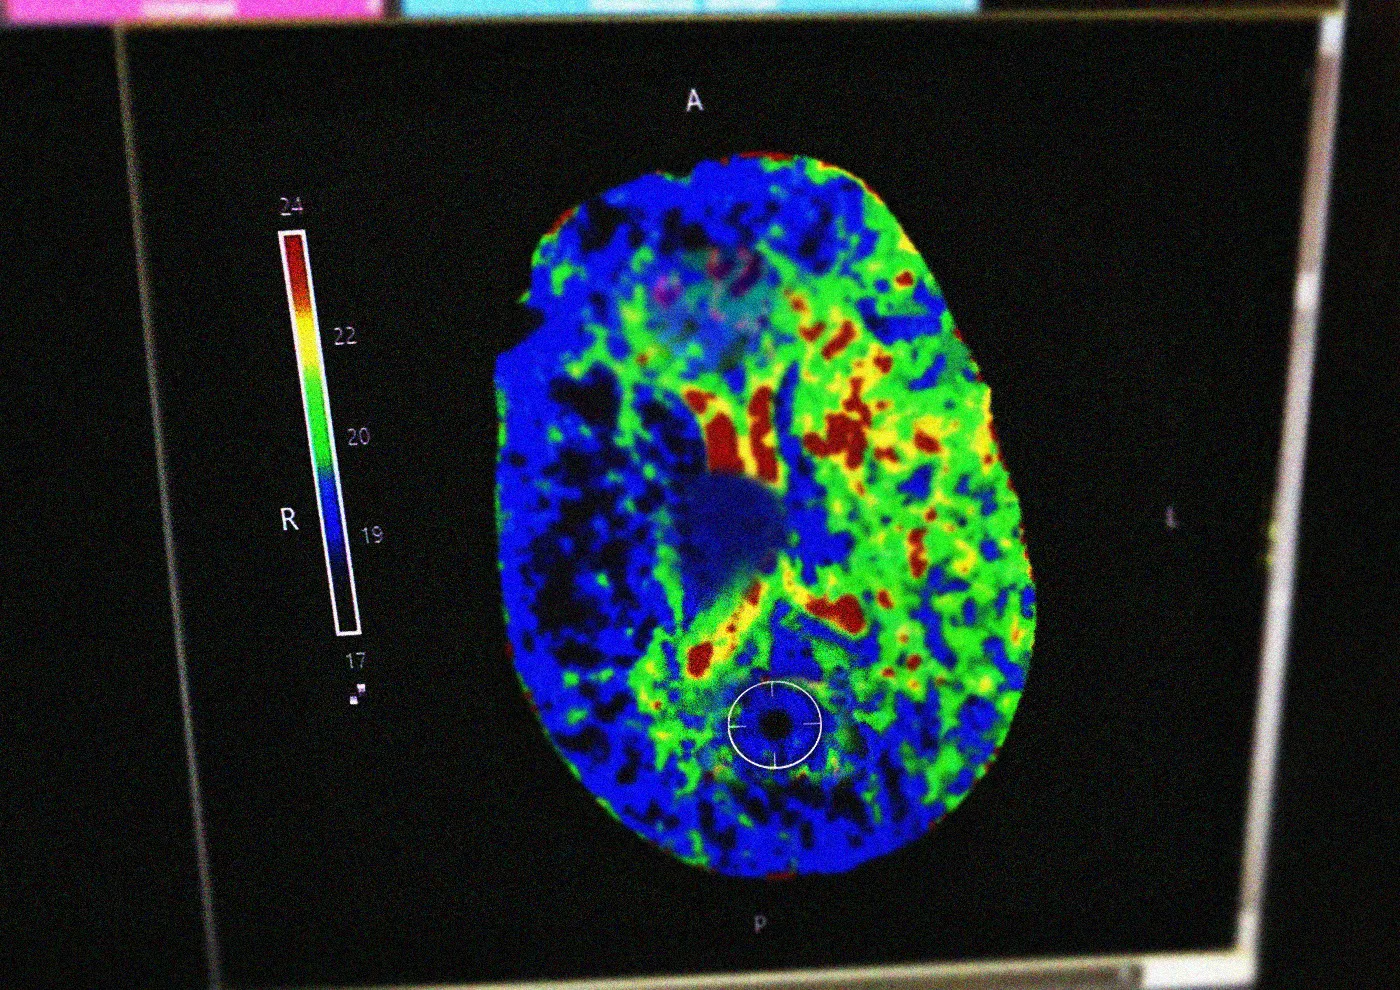

Это критически важно. Врачи подтвердили диагноз и начали готовить женщину к тромболизису — процедуре, которая растворяет тромб и восстанавливает кровоток. Так можно избежать повреждения мозга. Но у метода жёсткие сроки: успеть нужно в первые 3–4,5 часа после первых симптомов.

Тромболитическая терапия, или тромболизис, - это эффективный метод лечения инсульта. Препарат растворяет тромб, ставший причиной инсульта, и восстанавливает кровоток. Таким образом можно избежать повреждения мозга. Тромболизис проводится исключительно в стационаре в первые 3 - 4,5 часа после появления симптомов инсульта», - рассказал завотделением ОНМК Олег Сорокин.